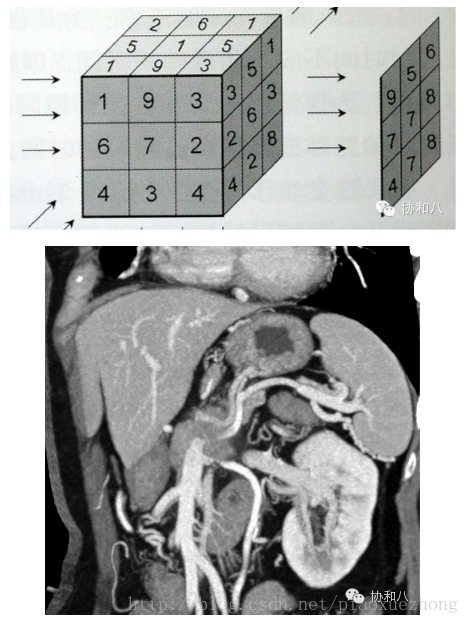

最大密度投影(MIP)

最大密度投影是将一定厚度(即CT层厚)中最大CT值的体素投影到背景平面上,以显示所有或部分的强化密度高的血管和/或器官,简单原理和图像是酱紫的:

由于这种方法显示的是一定层厚图像中CT值最高的体素,所以变化层厚会对图像产生影响:

层厚5mm 层厚15mm

肿么样,是不是觉得层厚5mm的MIP图像上门脉有狭窄,而层厚15mm的MIP图像上门脉是正常的?

由于MIP常用来显示血管的走行(问我为啥常用来显示血管?因为增强CT上血管比周围组织器官亮啊~),所以层厚的选择很重要,既不能太薄(血管的部分管腔可能在层厚以外),又不能太厚(周围组织器官有干扰),这是很考验放射科大夫的技术和临床经验的。